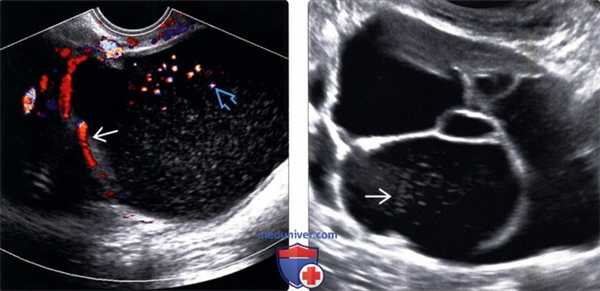

2. УЗИ при муцинозной цистаденоме и раке яичника:

• В-режим:

о Обычно многокамерные с тонкими перегородками

о Сосочковые разрастания встречаются гораздо реже, чем при серозных опухолях

о Слизь формирует низкоуровневые эхосигналы в камерах:

- Обычно имеются множественные камеры различной эхогенности

- Эхогенность различается в зависимости от концентрации слизи

о Наличие солидных компонентов увеличивает риск злокачественности

• Цветовая допплерография:

о В солидных компонентах отмечается кровоток

(Слева) Перегородки и диффузные низкоуровневые эхосигналы типичны для муцинозных цистаденом. На трансвагинальной цветовой допплерографии в продольной плоскости определяется кровоток в перегородках, а также артефакт потока, вследствие перемещения слизи.

(Справа) На трансабдоминальной ультрасонографии в камерах муцинозной цистаденомы определяются различные низкоуровневые эхосигналы, представляющие собой различные концентрации слизи.